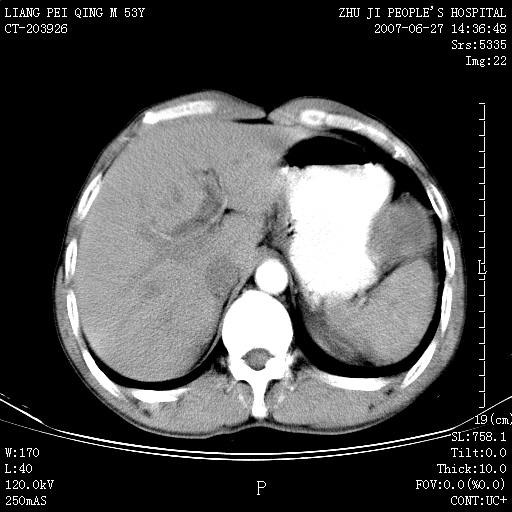

以下是引用余辉在2007-6-27 18:46:00的发言:[br]病灶多发,内可见大片状低密度区,病灶病灶等密度区轻度强化,动脉期后期病灶低密度区与高密度区对度增加,考虑1淋巴瘤2转移瘤3血管内皮细胞瘤(不知有否静脉期及延迟期扫描)

以下是引用zzzzhhhhaaaannnn在2007-6-27 20:44:00的发言:[br]脾脏 肋骨转移可能性大,下腔静脉内有癌栓

以下是引用狙击手在2007-6-28 10:35:00的发言:[br]1:定位:来源于脾脏。2:强化:强化,但不均匀。3:下腔静脉癌栓?下腔静脉充填不均匀与增强时间有关,延时即可明确。4:肋骨破坏?看起来并不确切。综上考虑几个最常见诊断:1;淋巴管瘤;2;血管内皮肉瘤(高度恶性,早期即可转移,常见肝,肺,骨)3;转移瘤(无特征性,只有肝或其它腹腔脏器有类似病变时,才可提示之)